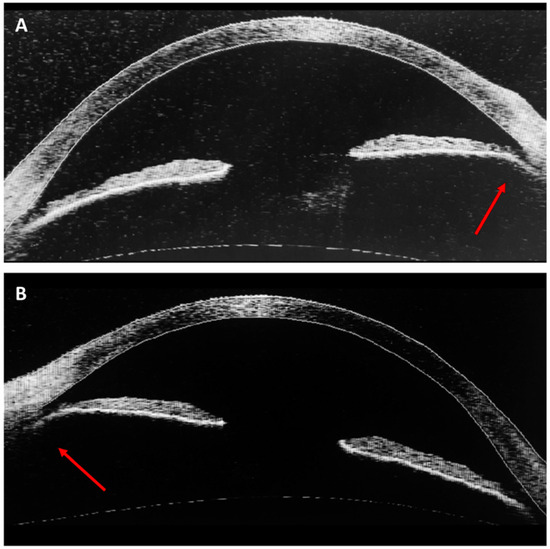

3. Case Report